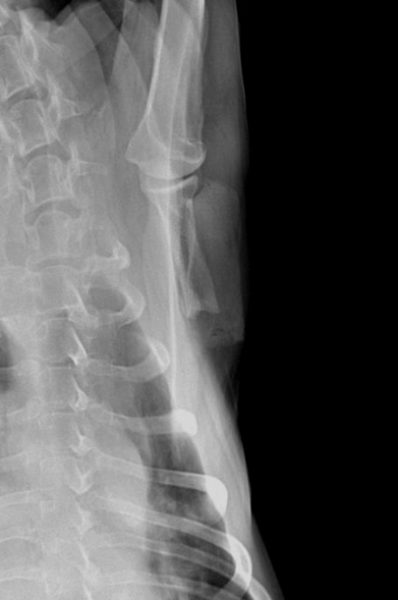

Les radiographies post-opératoires permettent de vérifier les traits de section et l’exérèse large de la portion modifiée de la scapula (fig. 7 et 8). Un pansement compressif est mis en place autour du thorax afin de limiter la formation de sérosités. Il est laissé en place jusqu’au retrait des points 12 jours après l’intervention.

Cinq mois après l’intervention, la chienne est revue en consultation pour détérioration de l’état général et appétit sélectif depuis 10 jours. Une faiblesse généralisée est présente, une dyspnée, une discordance ainsi qu’une légère tachypnée sont notées. Les propriétaires rapportent que la chienne utilise sont membre normalement mis à part le mouvement de circumduction de l’épaule qui n’a jamais disparu. La palpation ne permet pas de mettre en évidence une éventuelle récidive locale de la tumeur ce qui est confirmé par la réalisation de radiographies vigiles (fig. 11).